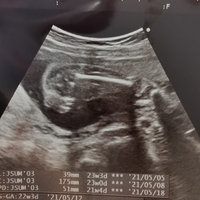

妊娠週 23w1d 大あくびの瞬間が撮れました☆ まぶたを閉じている様子もはっきり。 推定566グラム、頭の大きさは56センチだそうです。 ここまではっきりと顔を見られたのは初めてで、可愛さが増しました! おなまえ ま~ ねんれい 25 妊娠週 23w1d とてもMay 26, · 妊娠 4~11週目 ・妊娠5~6週目頃に婦人科を受診 ・NIPT検査は10週目~15週目まで検査可能 妊娠 12~15週目 ・妊娠届出書を提出して、母子手帳をもらう ・妊婦健康診査スタート(4週間に1回) ※妊娠初期のうちに出産場所を選んでおくと安心です! 妊娠Feb 22, 11 · 在胎29週で、緊急帝王切開で出産しました。出生時の体重は1166グラムで今は病院のnicuに入ってます。医師から、網膜症や脳出血、低酸素の影響

妊娠23週目 23w0d 6d のエコー写真とエピソード 妊娠6ヶ月 Cozre コズレ 子育てマガジン

医師監修 妊娠23週のエコー写真 物音に反応してびっくり マイナビ子育て

妊娠23週目エコー写真 胎動の様子 胎児の大きさや体重 妊娠中期 All About